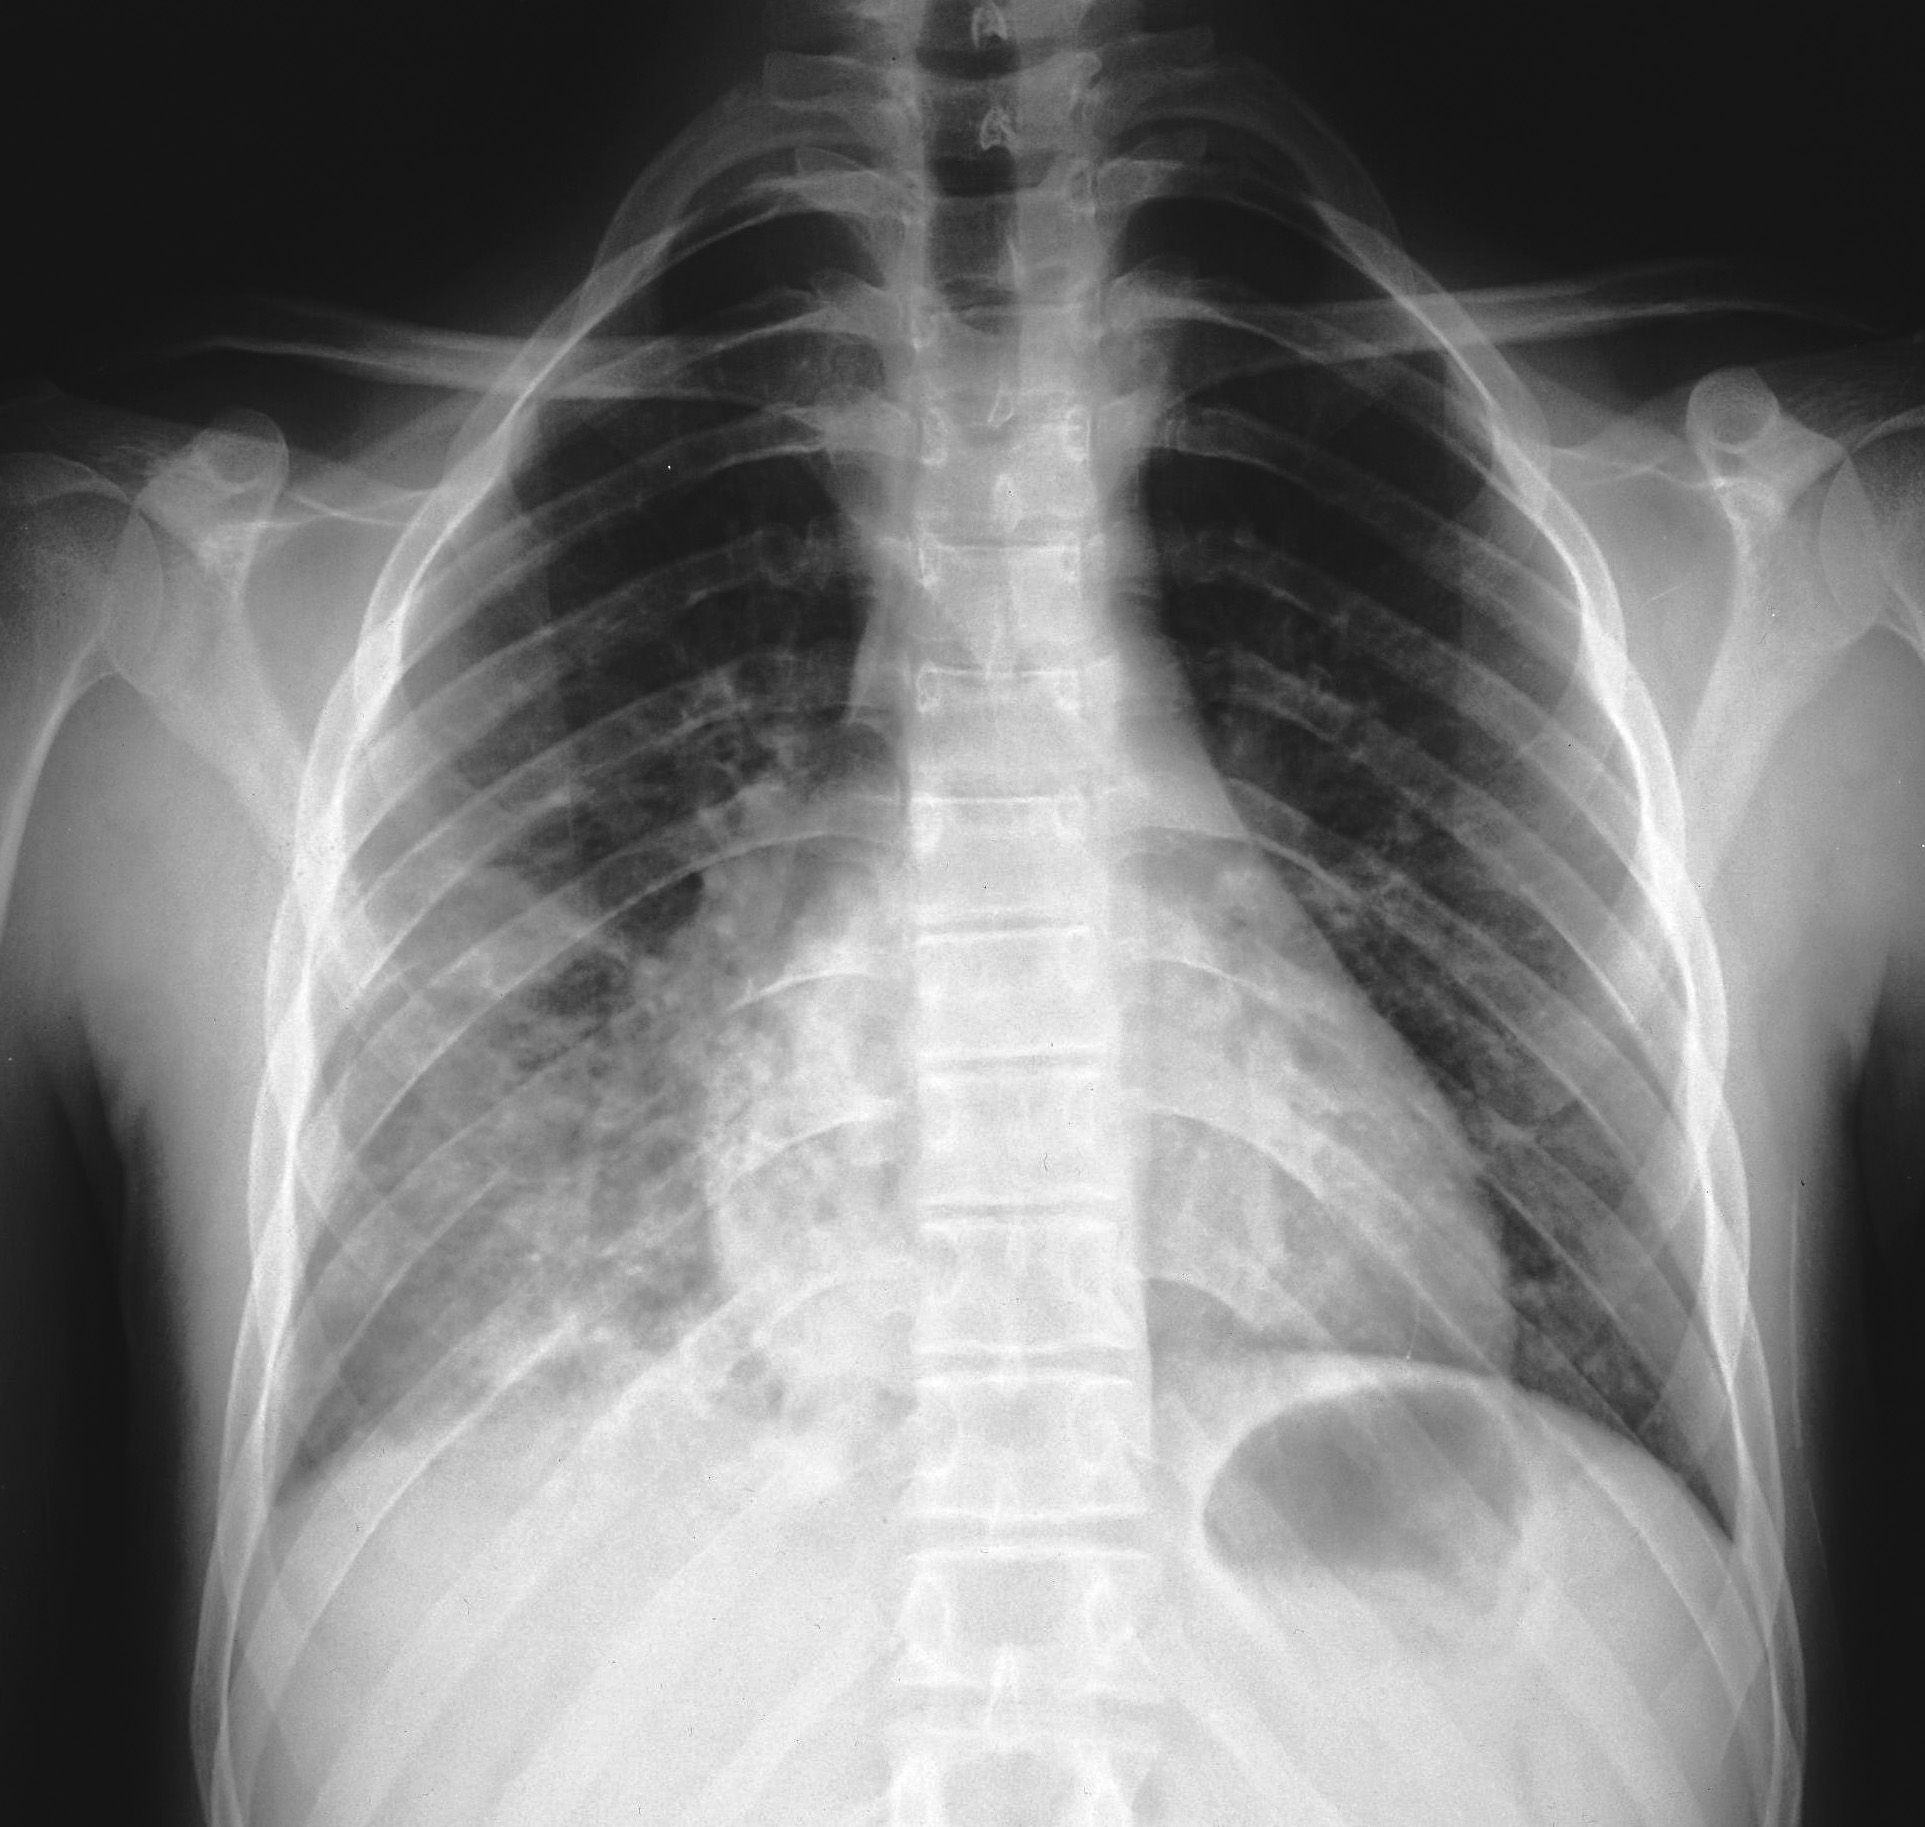

Nel complesso, cinque pazienti hanno presentato gastro-enterite con severa disidratazione, quattro bronco-polmonite con crisi dispnoiche, due bronco-ostruzione con crisi di cianosi, uno impetiginizzazione delle lesioni cutanee e, infine, un paziente congiuntivite purulenta. I pazienti italiani hanno presentato una maggiore percentuale di complicanze rispetto ai pazienti rom (Figura 2). Tra i pazienti italiani, due hanno presentato gastro-enterite mentre tre hanno sviluppato una broncopolmonite, confermata dalla radiografia del torace (Figura 3). Il bambino di un mese è stato trattato con immunoglobuline e.v. Nessun paziente ha presentato complicanze neurologiche.

Figura 3a.

Figura 3b.

Figura 3. Radiogramma del torace in proiezione antero-posteriore (a) e latero-laterale (b) in un paziente italiano di 15.3 anni. È evidente una polmonite interstiziale bilaterale, più accentuata a dx, con obliterazione dello spazio retrocardiaco, diagnosticata dopo 2 giorni dalla comparsa dell'esantema.